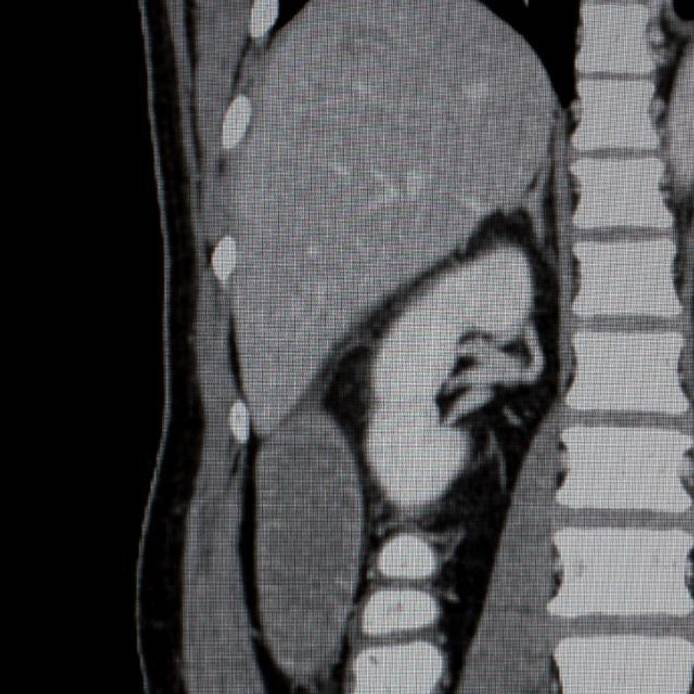

CT of abdomen

Postgraduate Certificate in Computed Tomography

This course has been designed to support the advancing practice of radiographers in the field of Computed Tomography (CT).